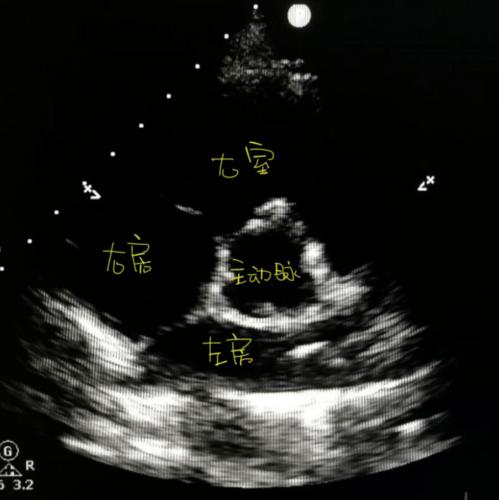

心尖五腔心切面

心尖五腔心切面,心尖五腔心切面图

心尖五腔心切面:主要用于显示右心室侧壁及调节束▲胸骨旁四腔心

心尖五腔心切面图

心尖五腔心切面示意图

超声心尖五腔心示意图

心脏五腔心切面图片